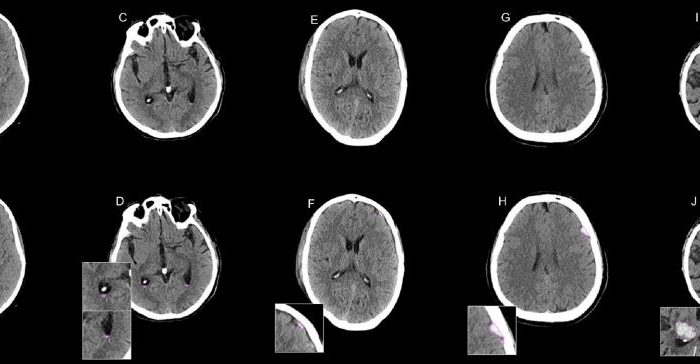

AI assistance improves radiology resident reader performance in CT diagnosis of intracranial hemorrhage

We are pleased to highlight a new publication from our group member Dr. Philipp Reschke in La Radiologia Medica, showcasing the significant value of artificial […]

Publication on deep learning-based intracranial hemorrhage assessment in non-contrast CT scans

DEI is happy to share our newly published study on deep learning-based intracranial hemorrhage (ICH) assessment in non-contrast CT scans published in La Radiologia Medica. […]